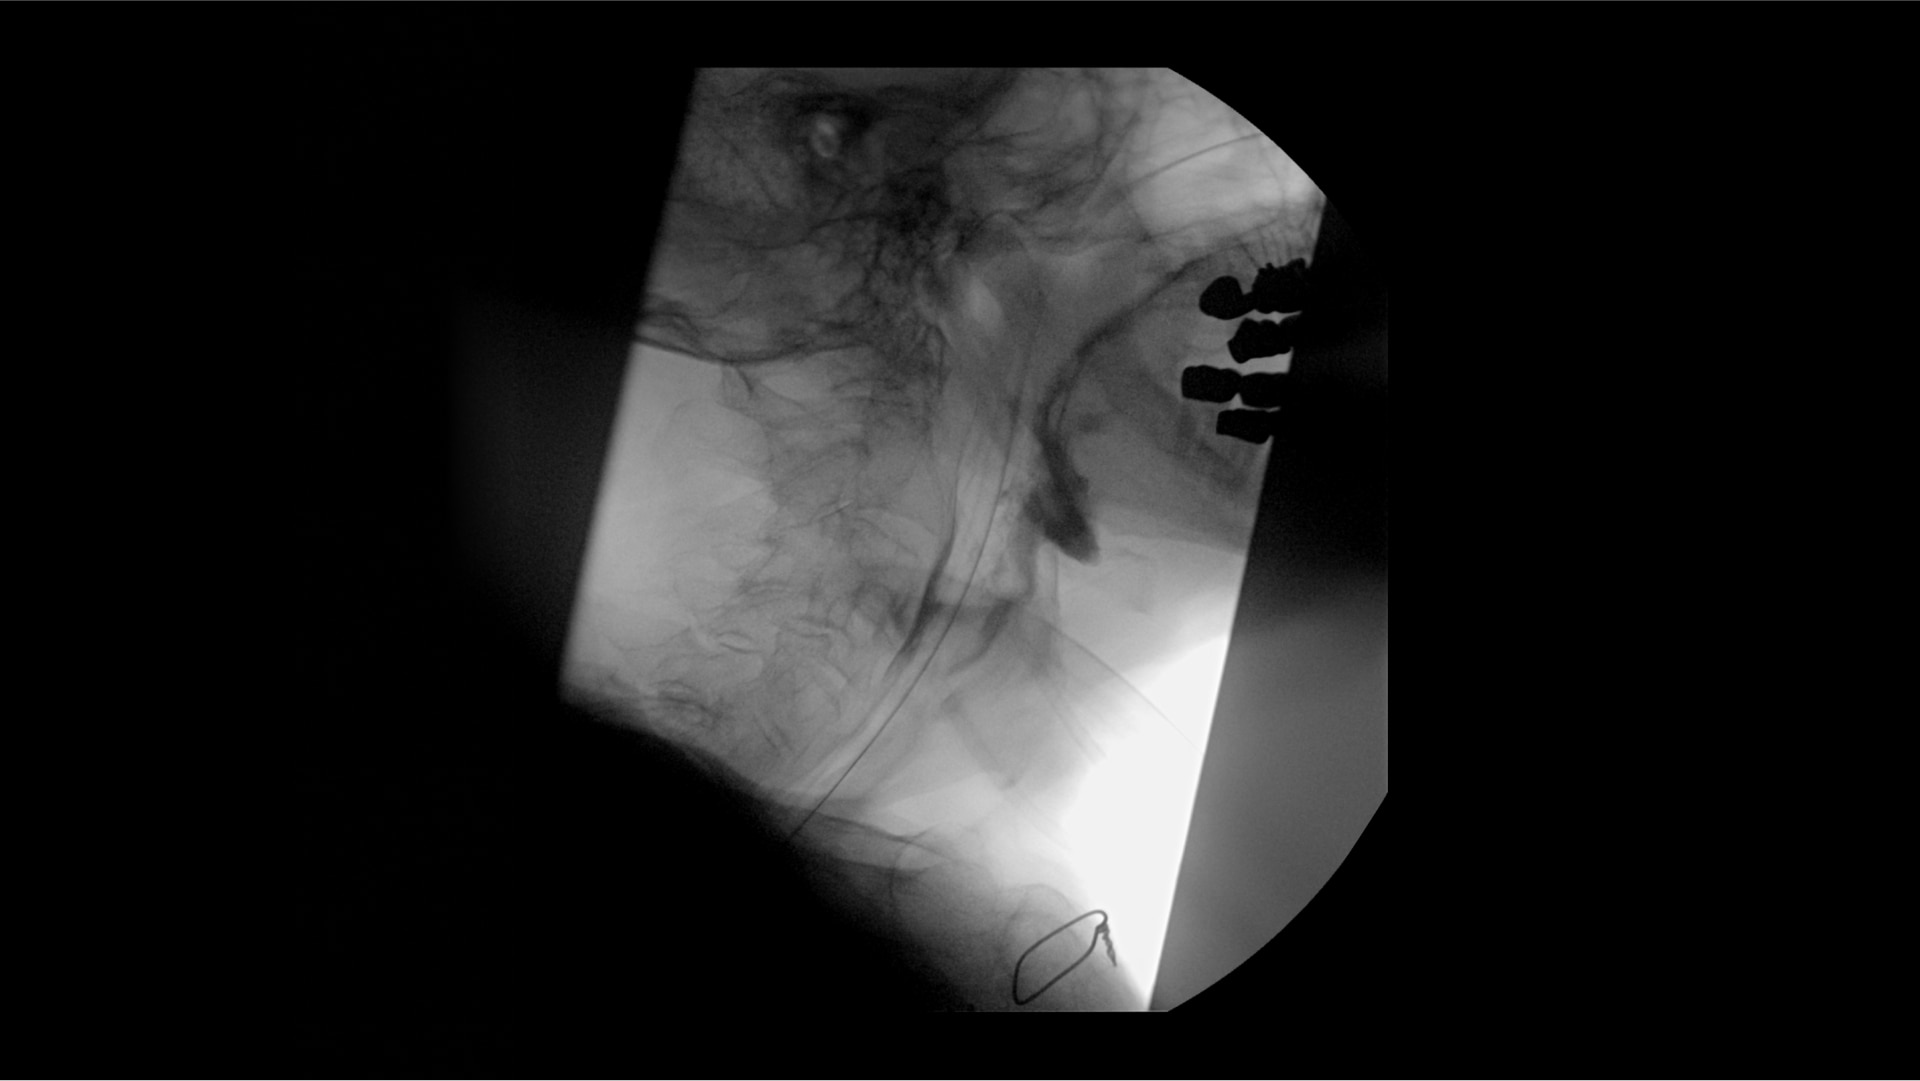

Clearly visualize the GI tract of patients, regardless of size, during a wide range of endoscopic procedures, including ERCP. OEC C-arms offer amazing image quality at low dose and provide enhancements for clear visualization during movement in soft tissue, such as during guidance of low-density drainage tubes or thin biopsy brushes. A large, clear display with comfortable viewing enables effortless workflow.

Complex gastrointestinal procedures require powerful imaging systems. OEC premium C-arms perform in a variety of procedures such as:

• Bariatric gastric embolism

• Pediatric congential duodenal

• Endoscopic retrograde cholangiopancreatography